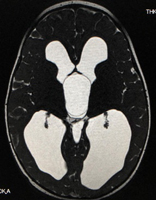

水頭症

水頭症とは病態を総称したものであり、小児脳神経外科領域で対応する水頭症は図(胎児水頭症ガイドラインより)の通りさまざまな原因によって発症します。そのために発症による日常生活動作の状態もさまざまです。

2つの画像のキャプション:胎児水頭症診断と治療ガイドライン(2010)より抜粋

水頭症はどのような状態であっても発症しているこどもの発達の足かせとなるため、治療が必要です。現在水頭症の治療には2つの方法があります。ひとつは「シャント術」と言われる短絡術、もうひとつは神経内視鏡を用いた「第三脳室底開窓術」です。